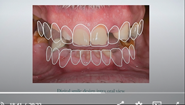

Figure 14 through Figure 18 show a partially dentate patient for whom a fully digital workflow was utilized. This 47-year-old male presented with root blunting and mobility of teeth Nos. 7, 8, and 9 (Figure 14). A thermoplastic clip was attached during the CBCT, and an intraoral scan was taken and superimposed on the CBCT. The case was then planned in the navigation planning software (Figure 15). Once the teeth were extracted, intraoral scanning was performed. The intraoral scan was imported into lab software (Figure 16), and a PMMA milled screw-retained prosthesis was fabricated. The prosthesis was placed the next morning (Figure 17). Two months later, a new intraoral scan was taken to capture the mature soft tissue, and the final milled titanium abutment and restoration were delivered (Figure 18).

Fig 17. Views of the milled PMMA screw-retained provisional restoration. Note the screw access holes in the incisor edges (left panel). (Images courtesy of Dr. Kim Knoll.)

Figure 17